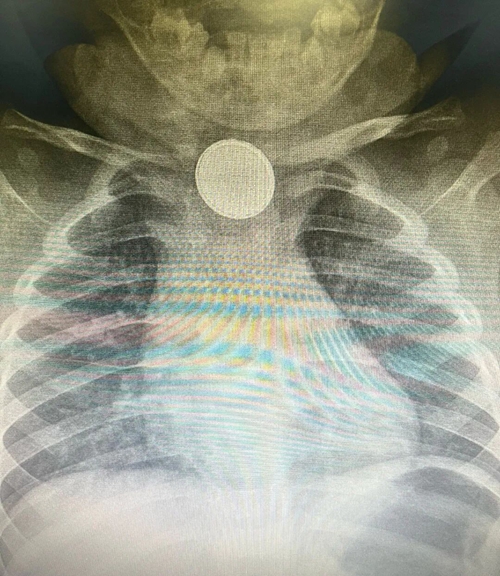

急診醫(yī)師憑借豐富經(jīng)驗,初步判斷是消化道異物,當即安排檢查。X 線片很快給出答案 —— 食管處可見出現(xiàn)一個類圓形高密度影。

類圓形高密度影